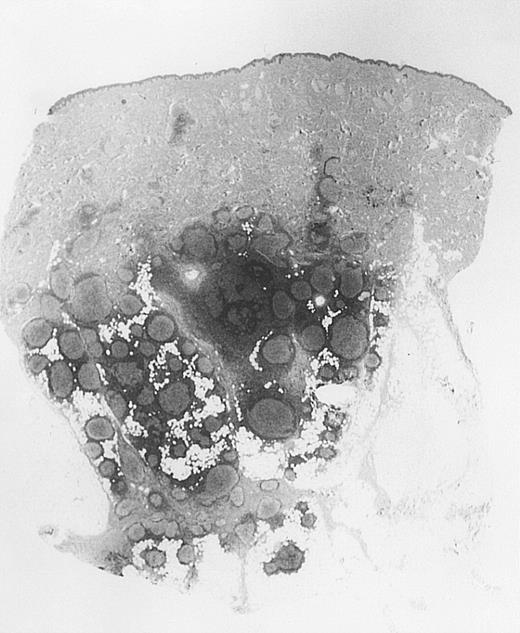

Bottom-heavy lymphoid infiltrate with prominent follicular pattern.

Located in the deep dermis and subcutaneous tissue (patient 9).

All cases of follicular lymphoma were classified as grade 2 according to the REAL classification. Histology showed bottom-heavy lymphoid infiltrates with prominent follicular pattern (Figures3 and 4). A well-formed mantle zone around most follicles was present only in 2 patients. In the other specimens the mantle zone was either reduced (11 patients) or nearly absent (2 patients) (Figure5). A clear-cut marginal zone was never observed. Tingible body macrophages within follicles were present only in 1 patient and were absent in the other 14 patients. Cytomorphology of follicles in all patients showed variable proportions of centrocytes (cleaved follicle center cells) and centroblasts (Figure6). The interfollicular areas revealed the presence of small lymphocytes and histiocytes admixed with a few larger cells and occasionally other inflammatory cells such as eosinophils and plasma cells.